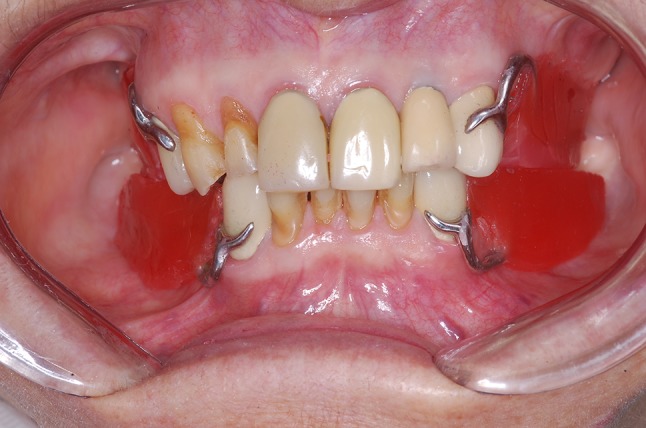

The dentures were made with poly(methylmethacrylate) resin (JET, Classico, Sao Paulo, Brazil). Gingival color characterization was determined based on the second color of the Tomas Gomez System (STG, VIPI, Pirassununga, Brazil). During installation, the crowns were cemented with glass ionomer cement (Ketac Cem, 3 M Espe, St Paul, USA). Subsequently, ball attachments of 4.1 mm (Singo Vinces, Campo Largo, Brazil) were installed, with a recommended torque of 32 N/cm. The O-ring retainers were captured one by one, in the oral cavity (Fig. 7a, b). Restorative procedures were performed on the remaining teeth (# 6, 7, 23, 24, 25 and 26) using a nano-hybrid composite resin, shade A3 (New Brillant, Vigodent, Coltene, Rio de Janeiro, Brazil). After completion of all rehabilitation procedures; the occlusion was monitored and adjusted, if necessary.

Fig. 7.

O-ring retainers in position in the a superior and b inferior RPD